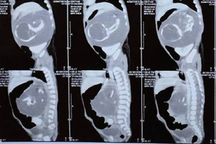

Theo thời gian, thai nhi càng lớn thì kích thước khối bướu vùng cổ cũng tăng lên. Đến khi thai 31 tuần, kích thước khối bướu tăng lên 95x58x95mm, ảnh chụp MRI cho thấy có dấu hiệu chèn ép nhẹ vùng hầu họng, nhưng nhu mô não của bé không bị tổn thương.

Khối bướu xuất hiện từ tuần thai thứ 21 và phát triển khổng lồ lúc gần sinh, khiến bé trai bị chèn ép đường thở nguy hiểm (Ảnh: BV).

Ngày 25/5 (thai gần 37 tuần), bác sĩ tiền sản và bác sĩ nhi đồng khám, chụp MRI não và khối bướu để đánh giá lại lần cuối tình trạng sức khỏe của mẹ và bé. Lúc này, khối bướu đã rất to, có dấu hiệu xâm lấn, chèn ép vùng hầu miệng và hầu thanh quản.